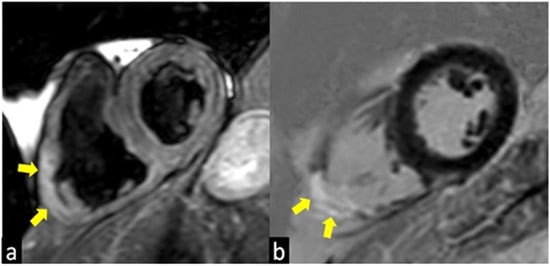

3.2. Cardiac MRI